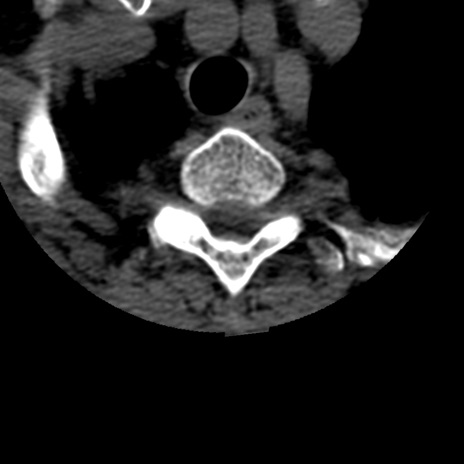

症例50 頚椎CT(横断像)

矢状断像